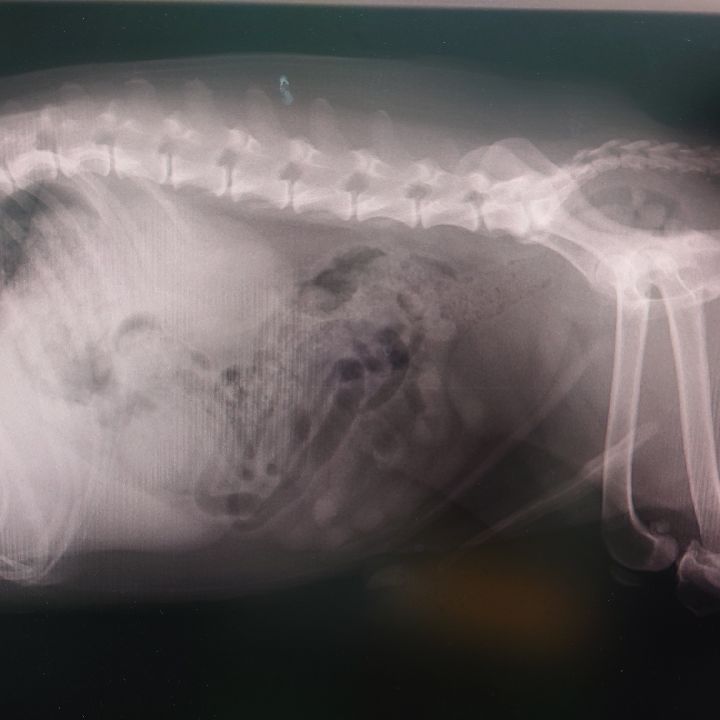

獣医師が教える‼ペットの夏対策!